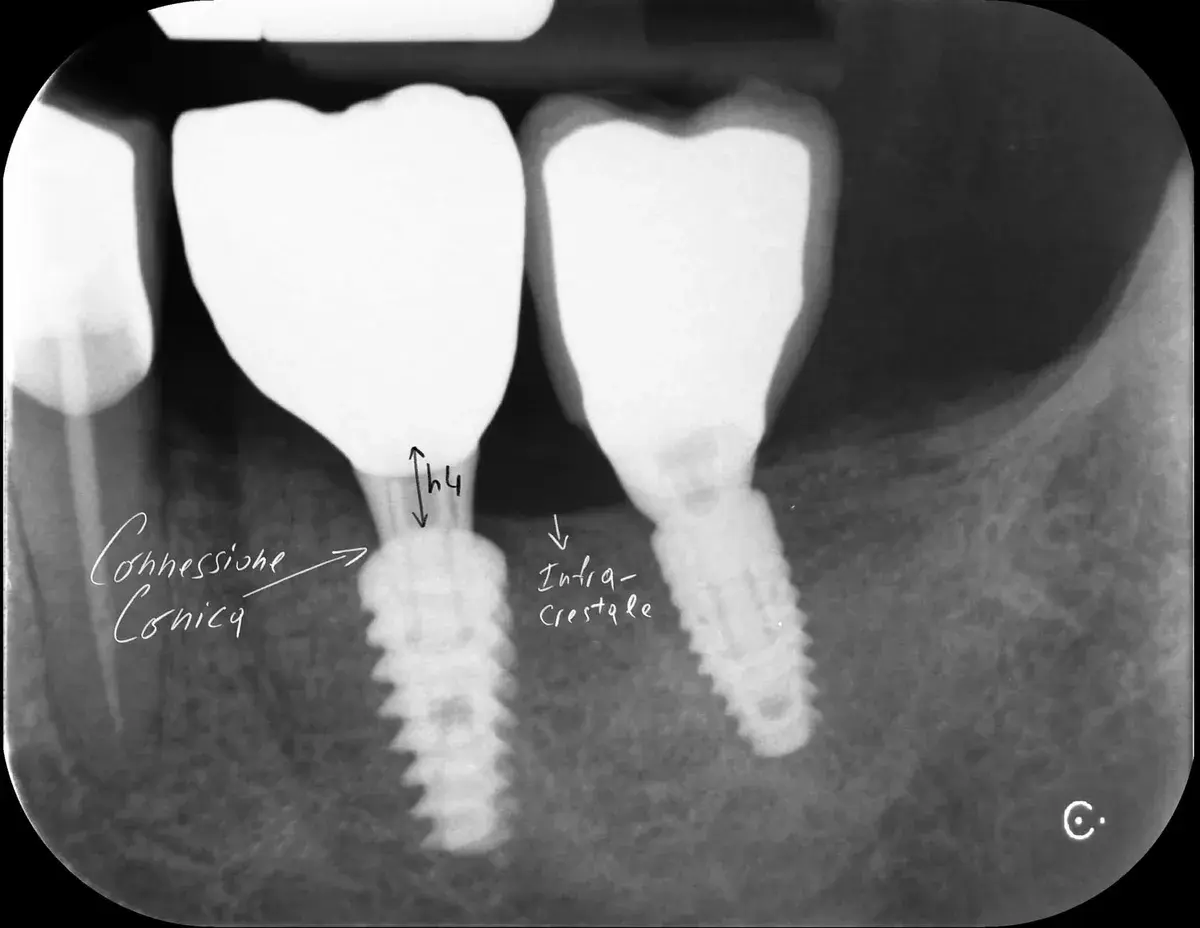

Bone-level, tissue-level, connessione conica: la profondità corretta cambia con il tipo di connessione. Perché sbagliarla causa riassorbimento osseo.

Microgap, perdita ossea crestale e stabilità meccanica: perché la connessione implantare non è un dettaglio. Cono Morse vs flat a confronto.